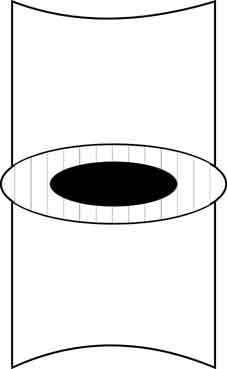

В позвоночных дисках картина несколько иная, можно сказать, противоположная. В норме (чаще в молодом возрасте) межпозвонковый диск представляет собой как бы тугую амортизирующую подушку, состоящую из фиброзного кольца, содержащего в центре пульпозное ядро. Волокна кольца очень прочны и при условии поддержки изнутри пульпозным ядром обеспечивают позвоночному сегменту хорошую стабильность.

Но при дистрофических процессах в диске ядро уменьшается в размерах, связки фиброзного кольца ослабевают без поддержки изнутри и в сегменте возникает гипермобильность – так называемая ортопедическая стадия остеохондроза.

Тело вышележащего позвонка обретает дополнительную степень свободы, и может смещаться в горизонтальной плоскости чаще кзади, что обусловлено строением дугоотросчатых суставов (так называемый «дегенеративный сдвиг»). Кроме того, увеличивается и вертикальная подвижность краёв соседних позвонков, что при форсированных сгибании и разгибании приводит к возникновению отрицательного давления в «полости» межпозвонкового диска и как следствие этого к появлению «вакуум-феномена».